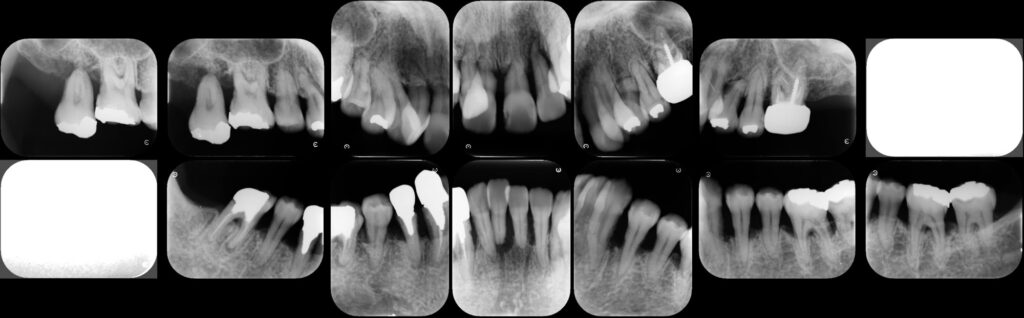

歯周再生療法 精密根管治療 歯周矯正治療 ジルコニアセラミック治療